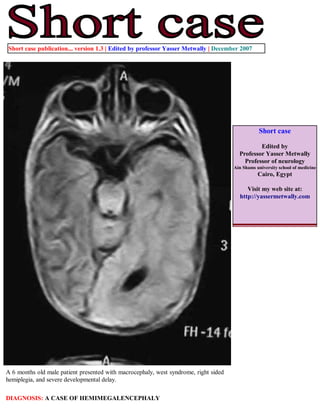

Download to read offline